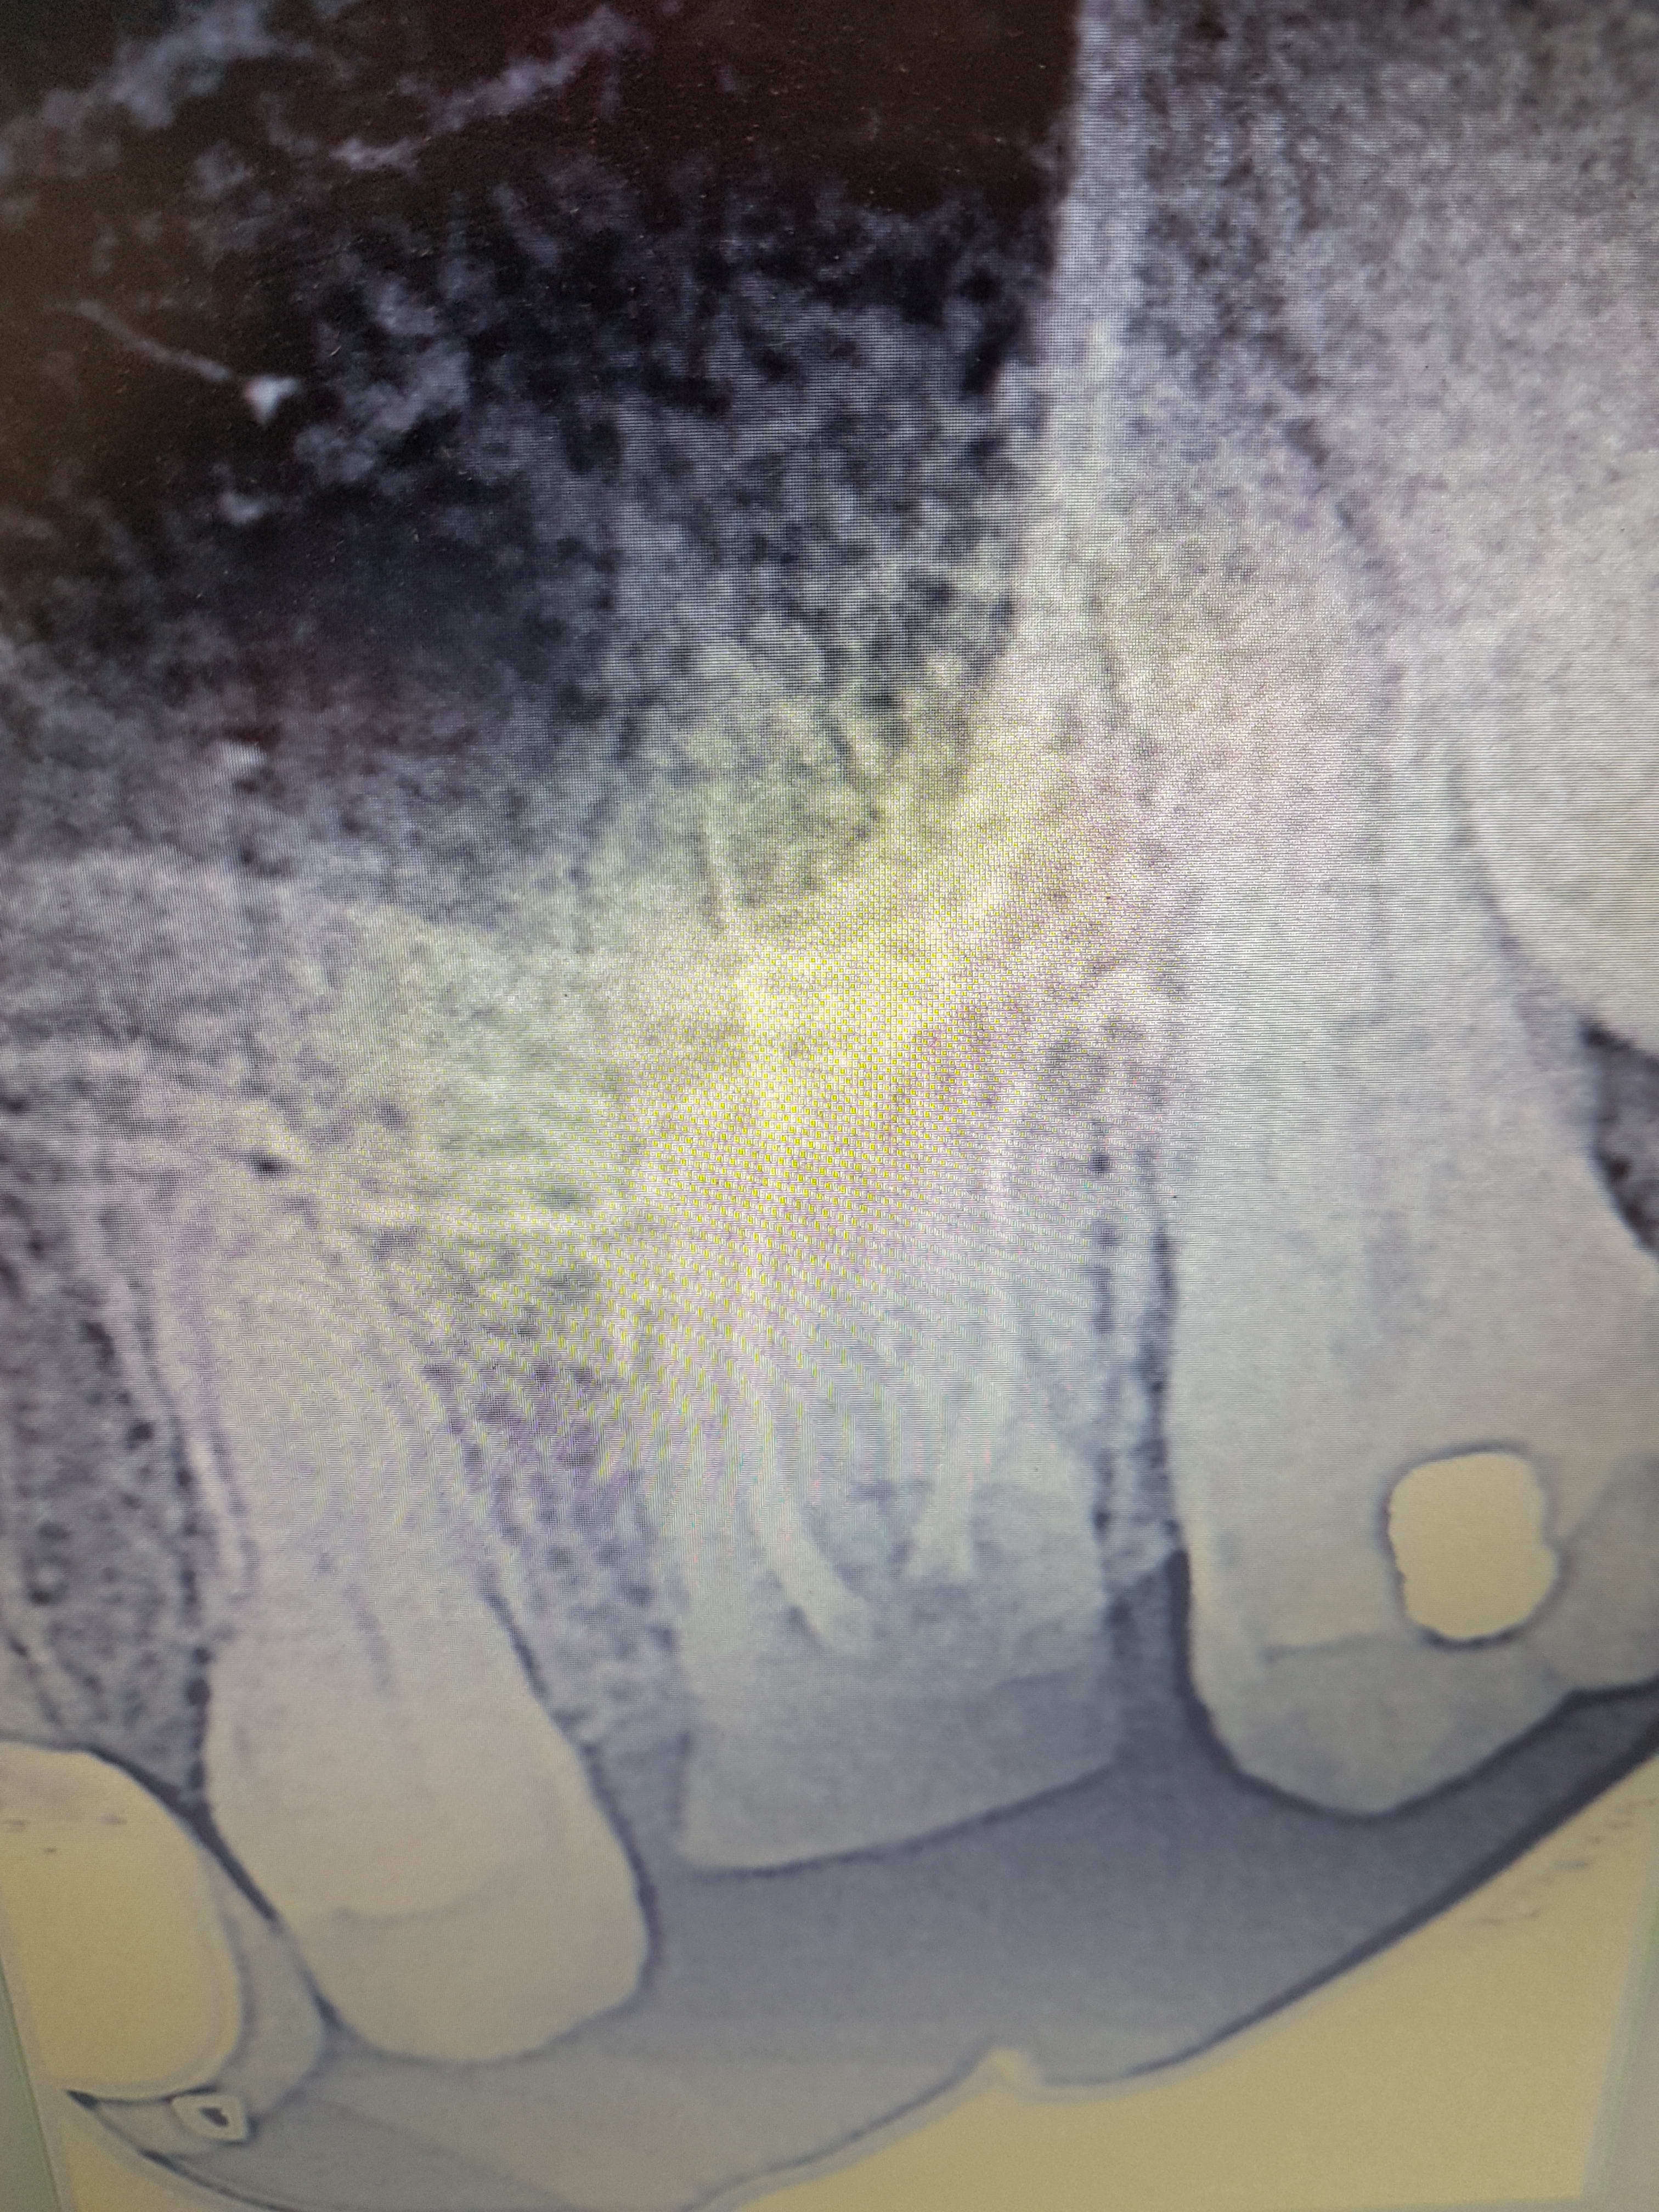

Un autre exemple de l'utilisation des versah. Cas d'EII sur 26, Forage dans le septum et osseodensification. Souleve' de sinus de 5mm mais sans comblement. Controle à 7 jours, aucune douleur post op.

20171018 094131 hjcxwj - Eugenol

20171018 094139 iocwui - Eugenol

20171018 095402 zrdzxf - Eugenol